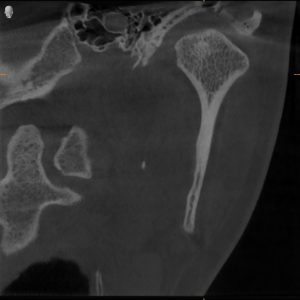

MRI confirmed bilateral disc displacement without reduction — both jaw joints had discs that had slipped out of position, causing compression and inflammation.

Clinical & Radiographic Findings

- Bilateral disc displacement without reduction

- Restricted opening (31 mm → improved to 47 mm)

- Myofascial tenderness and deep bite

- Significant parafunctional clenching pattern

Bilateral TMJ dysfunction with disc displacement and muscular hyperactivity.